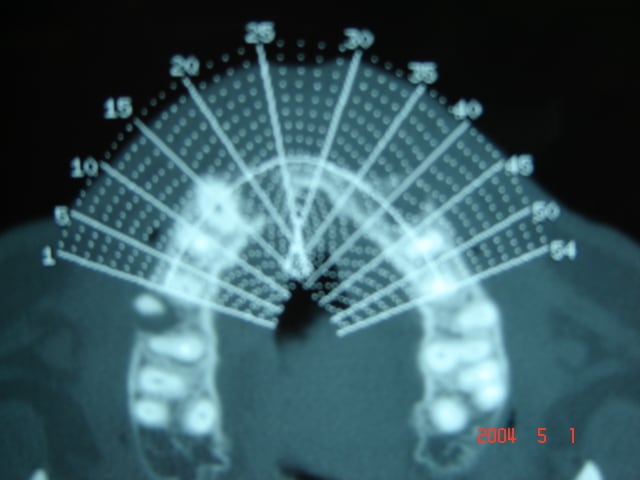

09/01/2006 à 15h28

et le scanner .

Imagerie ghomrani 002 mjfu7r - Eugenol